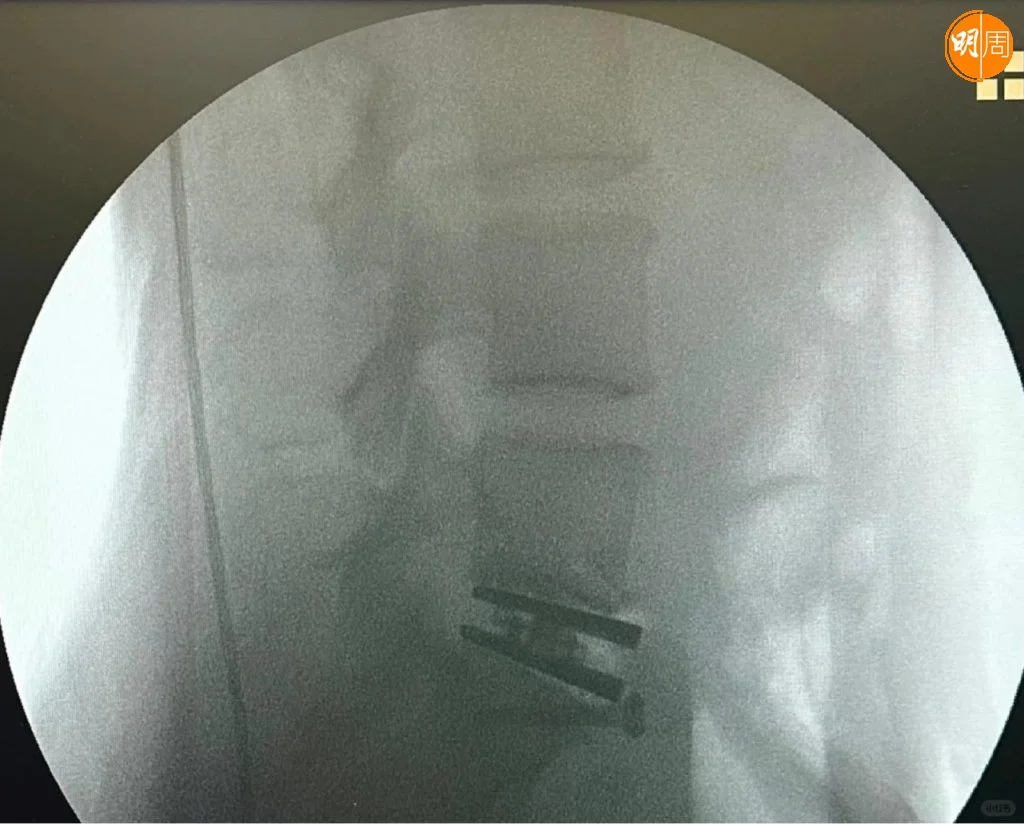

徐濠縈(阿徐)近日也入院做手術,昨晚(24日)阿徐在社交平台貼出X光照片,以及在手術室和醫護人合照,相中見阿徐露笑容,神情輕鬆,同時她上載花束及營養品等照片,此外,亦見到「加油!媽媽」的祝福句,似是囡囡陳康堤送給媽媽的打氣語句。

阿徐留言表示,今次是她自生女後最重要的手術,自揭前年曾接受切除椎間盤部分的手術,但下背仍然疼痛不已。熱愛跑步的她又謂,這2年過得特別難,她要停止重量訓練,並影響到她的日常生活,每當打噴嚏時,都有劇痛感覺,她的醫生建議做椎間盤置換手術。

阿徐今日(25日)亦有在小紅書發文,附加了臥在醫院病牀上雙手舉V的照片,她看來精神很好,身旁有到來探病的3大猛男謝霆鋒、馮德倫和劉浩龍,不知是否Eason負責揸機拍攝。阿徐以「手術成功」為題,並留言透露:「『人工椎間盤置換術』是一早安排今個6月份做的手術」、「康復時間需要幾個月」,網民都祝阿徐和Eason早日康復。